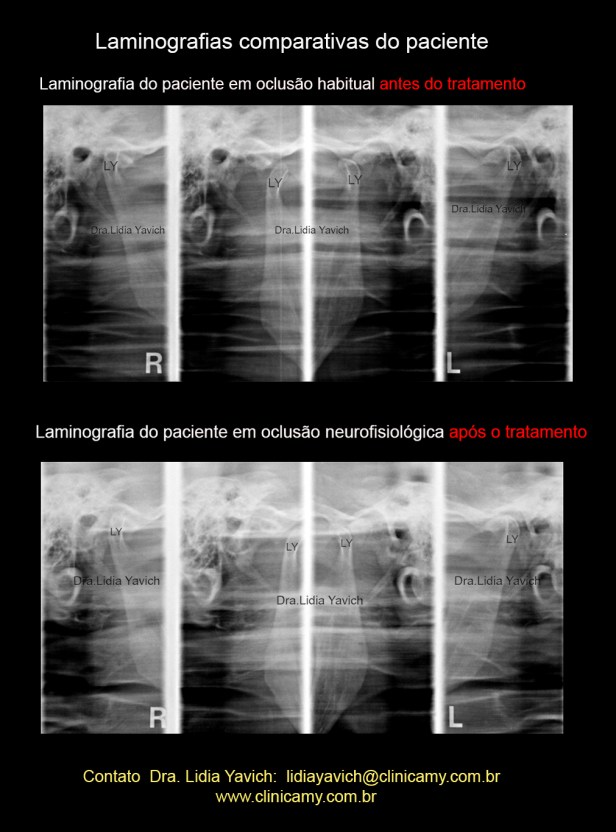

Laminografia das articulações temporomandibulares direita e esquerda em boca fechada e aberta em oclusão habitual antes do tratamento neuromuscular fisiológico.

Laminografia das articulações temporomandibulares direita e esquerda em boca fechada e aberta em oclusão neuromuscular fisiológica após o tratamento.

Comparação das laminografias das articulações temporomandibulares direita e esquerda em boca fechada e aberta: em oclusão habitual e com o DIO dispositivo intraoral.